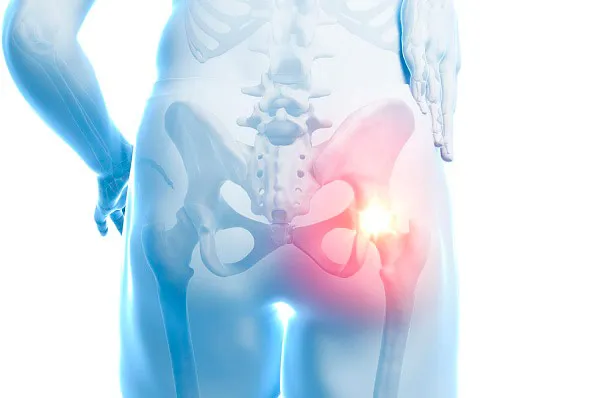

골반 부위에 통증이 나타나면 흔히 "파"로 알려진 "절뚝거림"으로 이어지는 경우가 많습니다. 고관절 통증은 크게 세 가지 방향으로 나뉩니다: ▲서혜부(사타구니) ▲측면 ▲후면으로, 각각의 방향에 따라 의심되는 질환이 달라집니다. 그중 가장 많이 보고되는 증상은 사타구니 통증입니다.

고관절 발달 이형성증이나 대퇴골두 충돌 증후군이 있을 경우, 대퇴골두의 무혈성 괴사가 말초 골절로 확장되면 사타구니 부위에 통증이 발생하는 것이 보통입니다. 고관절 외측의 통증은 주변 연부 조직의 손상 또는 염증으로 인한 대전자 통증 증후군(GTPS)과 관련이 있으며, 고관절 후방 통증은 주변 근육의 긴장이나 비대로 인해 이상근 증후군이 좌골 신경을 압박하는 상황에서 발생할 수 있습니다.